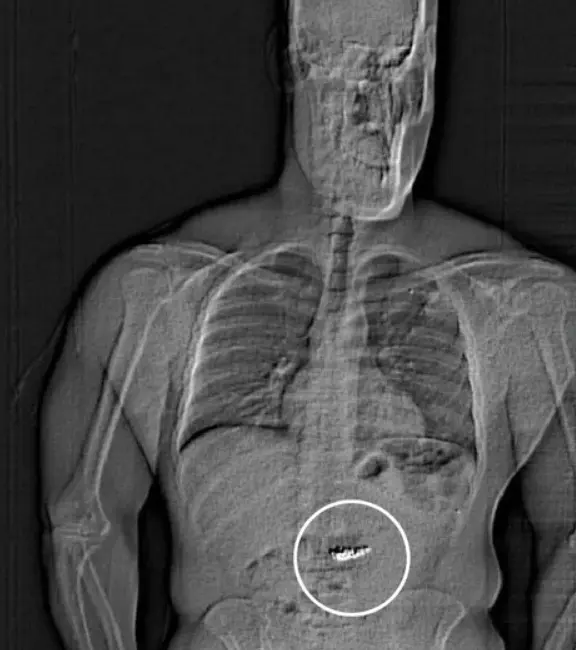

That spontaneous remark led authorities to conduct a body scan, revealing foreign objects moving through his digestive tract—suspected to be the missing Tiffany earrings.

“These foreign objects are suspected to be the Tiffany & Co. earrings taken in the robbery but will need to be collected by WCSO after they are passed through Gilder’s system before confirming,” the arrest report stated.